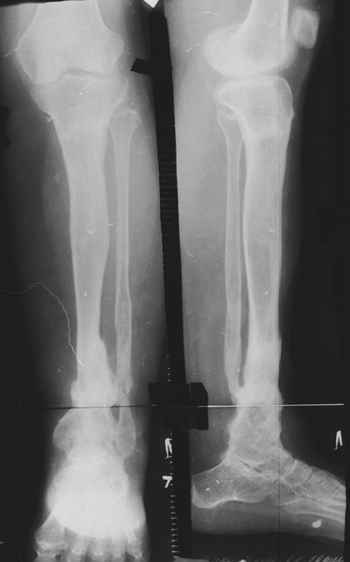

Случай, который я представляю, был сделан мной около 20 лет назад в Кургане.

Женщина 28 лет, пошедшая 13 предыдущих оперативных вмешательств по-поводу ВПБ имела 9 см. укорочения.

На первом этапе аппаратом Илизарова закрыто устранена деформация голени.